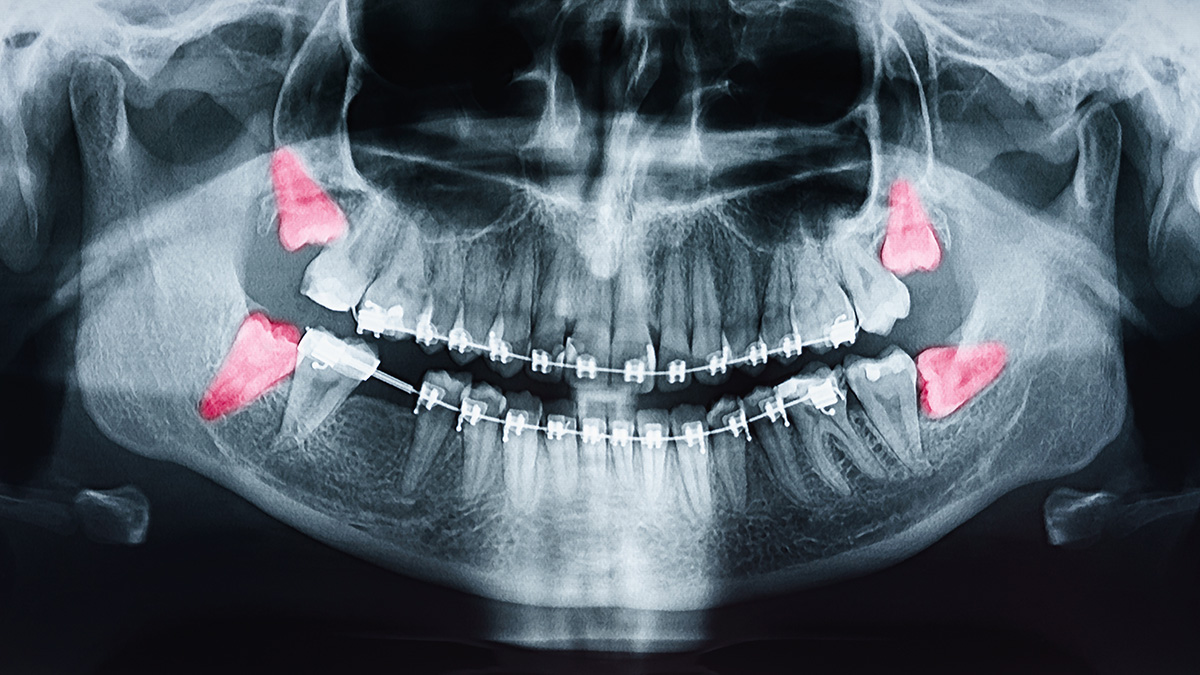

Routine evaluation of wisdom teeth usually begins in the late teenage years or early twenties, when third molars are developing and their path of eruption can be assessed. A clinical exam combined with a panoramic X-ray or other imaging helps your dentist determine whether there is enough space and whether the teeth are likely to erupt normally. Early evaluation allows the dental team to monitor development and recommend timely intervention if problems are anticipated.

Decision-making begins with a thorough clinical exam and diagnostic imaging to evaluate tooth position, root formation, proximity to nerves and sinuses, and the health of adjacent teeth and bone. The dentist will assess whether a wisdom tooth is fully erupted, partially erupted, impacted, decayed, or associated with gum problems or cysts. These factors, plus the patient’s age, medical history and symptoms, guide the recommendation for extraction or observation.

Impacted wisdom teeth can exert pressure on neighboring molars, increase the risk of decay and periodontal problems in adjacent teeth, and in some cases contribute to root resorption or localized bone loss. These issues can complicate long-term dental health and may jeopardize the stability of nearby teeth. During orthodontic treatment, the presence of impacted third molars is evaluated to determine whether removal would benefit overall treatment goals and long-term alignment.

Decisions about extraction in the context of orthodontics are individualized and often made in collaboration with the orthodontist and the dentist or oral surgeon. The care team will consider timing, the position of the wisdom teeth, and the status of the patient’s bite before recommending monitoring or removal. Clear communication between providers ensures treatment plans support lasting oral health and function.